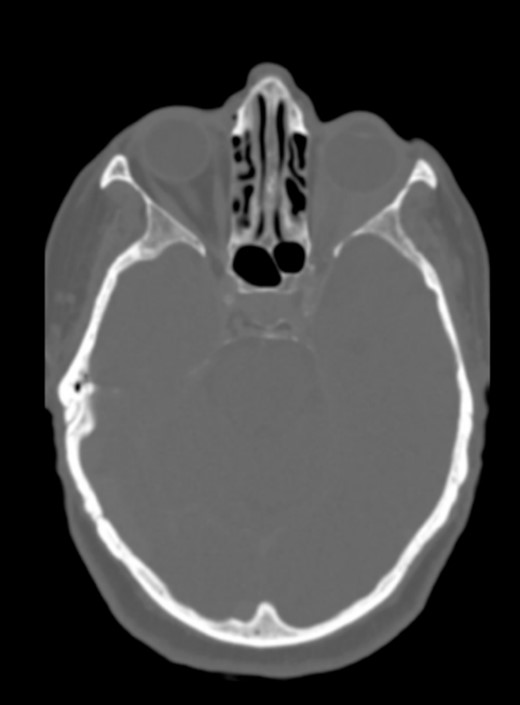

The CT scan displayed a tissue infiltration and bulking of the left superior and lateral extraocular rectus muscle (Fig. 1).

Axial and coronal cerebral CT scans show enlargement of the left lateral and superior rectal muscles (A–B), with slight enhancement (C–D).